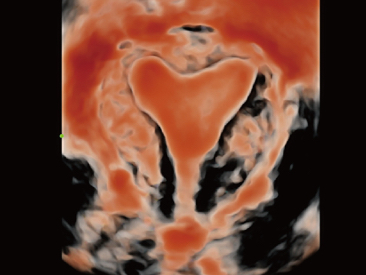

Desde que se fund├│ la compa?├Ła, Mindray ha explorado incansablemente nuevas formas de mejorar la confiabilidad del diagn├│stico. Con la revolucionaria tecnolog├Ła de ZONE Sonography?, la nueva plataforma ZST+ de Resona?7 lleva la calidad de la imagen por ecograf├Ła a un nivel superior mediante el procesamiento de datos de canal y la adquisici├│n de zona.

Adem├Īs de la calidad de imagen de primer nivel, Resona?7 tambi├®n mejora las capacidades de investigaci├│n cl├Łnica con el revolucionario V?Flow para la evaluaci├│n hemodin├Īmica vascular y con la adquisici├│n de planos m├Īs inteligente a partir de conjuntos de datos 3D para el diagn├│stico del SNC fetal. Al combinar el funcionamiento multit├Īctil basado en gestos m├Īs intuitivo y todas las caracter├Łsticas cl├Łnicas esenciales, Resona?7 realmente lidera las novedades en innovaci├│n de ecograf├Łas.